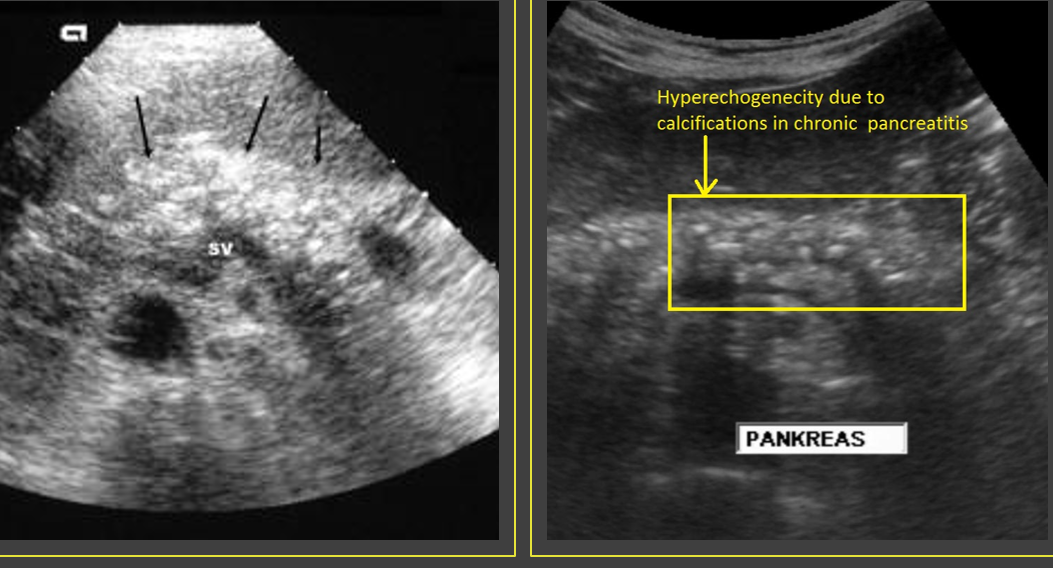

Sonographically, chronic pancreatitis may appear _____ or ______ with increased ______, size _____, ______ borders, and ______ duct

localized; diffuse; echogenicity; reduced; irregular; dilated

What is a classic finding of chronic pancreatits?

Calcification